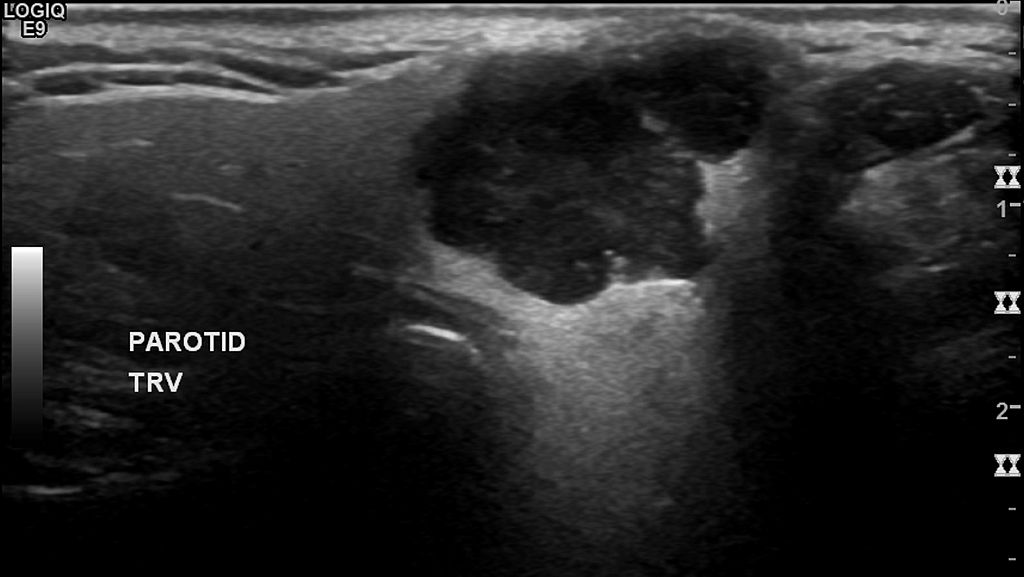

Warthin Tumor

Warthin tumor is a benign cystic tumor with a stroma that resembles a lymph node and many lymphocytes.

Warthin tumor is also known as papillary cystadenoma lymphomatosum.

Warthin tumor is the second most common salivary gland tumor.

Warthin tumor occurs almost invariably in the parotid.